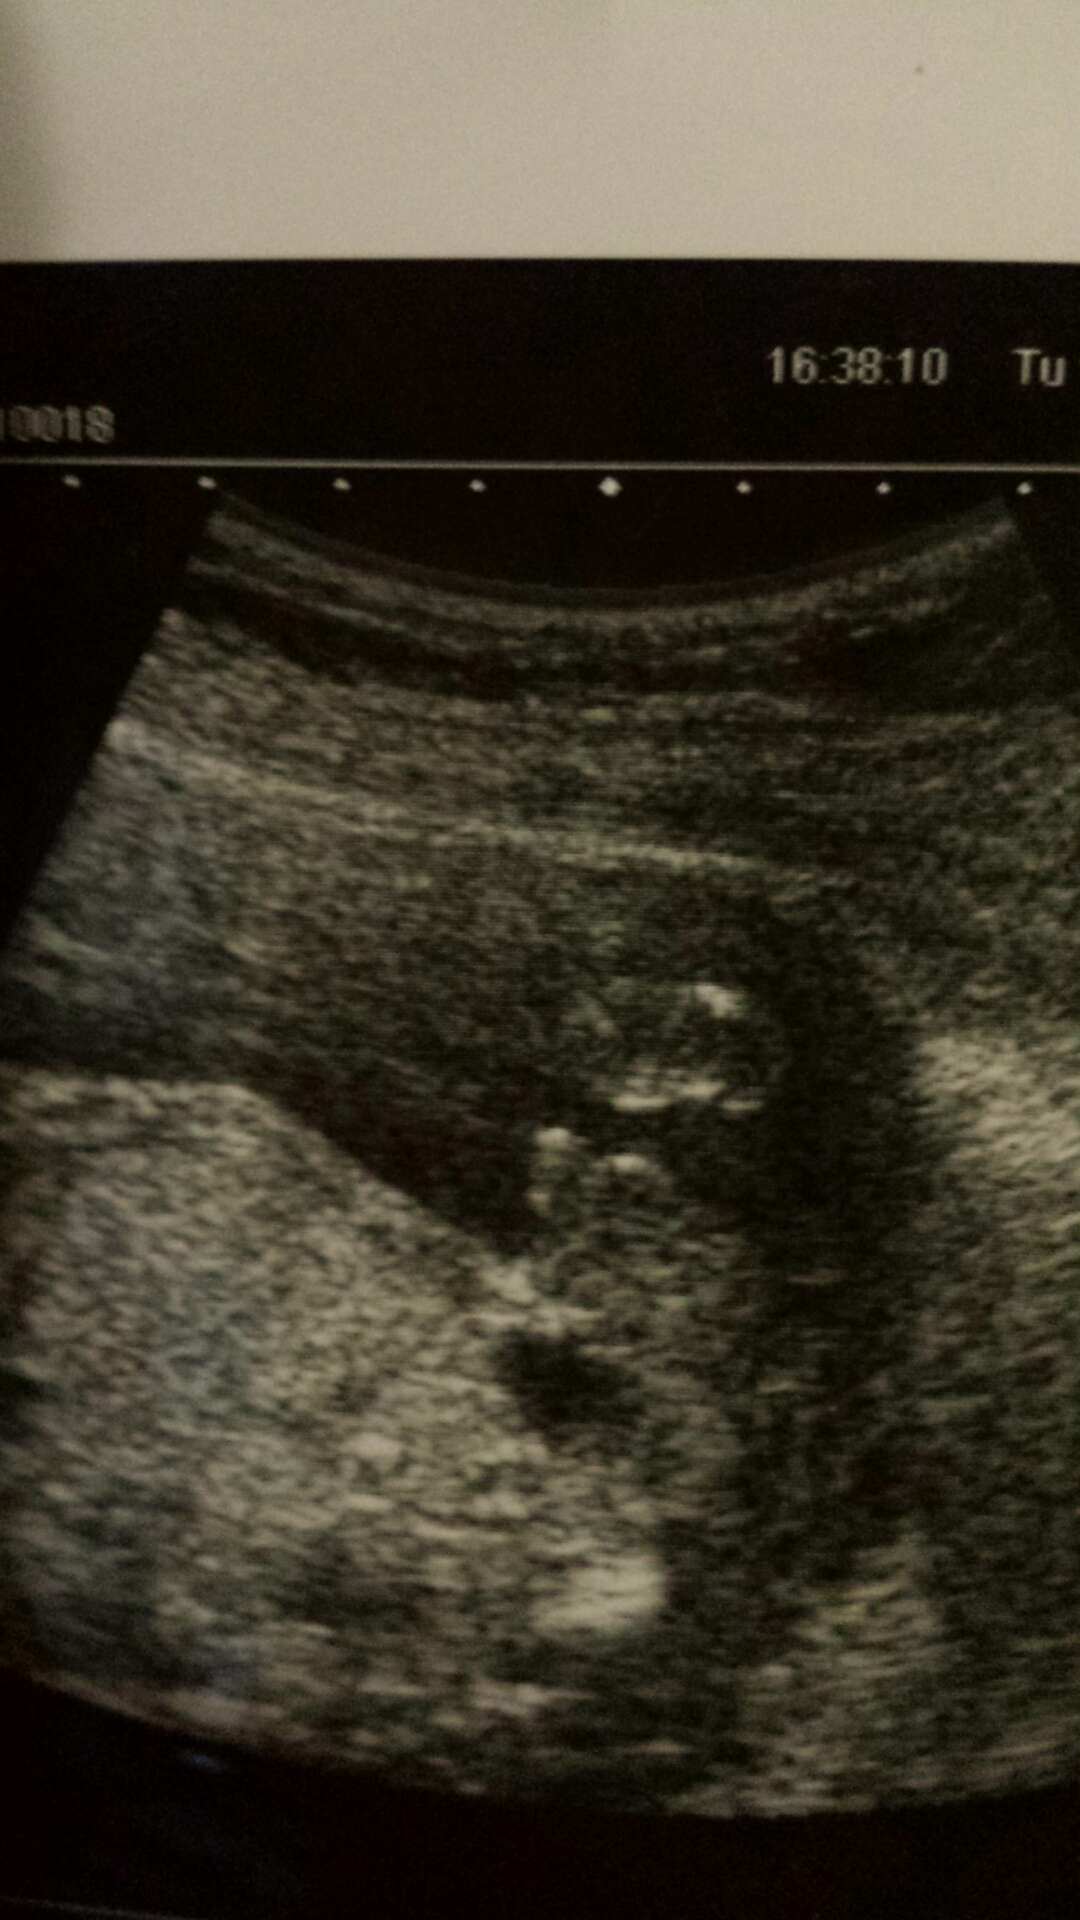

I have posted 2 photos will you plz zoom in and look closely to where i have circled...what appears as very obvious boy parts when you zoom in it loooks like the cord that continues through the bottom of baby and flips over and continues to go through end ofpic...in the other photo zoom in and it clearly looks like girl parts...labia with clitoris in the middle i was 20 weeks what is ur thoughts?Attachment 22387